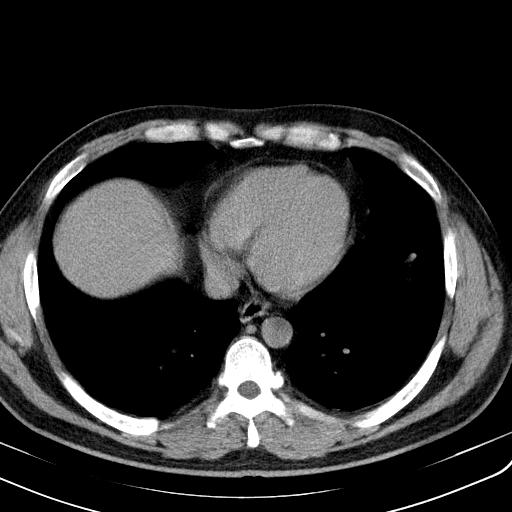

一周后复查胸片基本正常

补充一下各种检查结果,病人无痰,胸闷,ppd及结核抗体阴性,wbc7.5x10的9次方,血沉22mm/h,crp及抗链o阳性。

哦cea8

经一周抗炎抗病毒治疗复查胸片示病变大部吸收,基本恢复正常,未做气管镜检查,考虑为炎性变或霉菌感染。